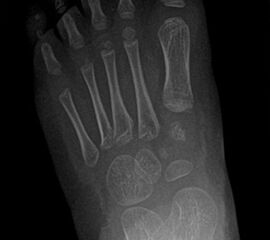

• Röntgen des dargestellten Falles 3 Monate post OP (Bild 25,26)